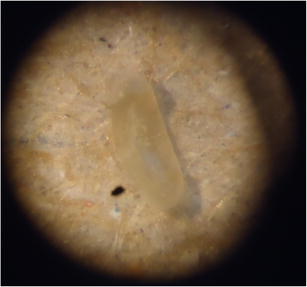

What is Ivermectin Human Toxicity Namibia. Ivermectin is widely used in veterinary medicine as an anthelminthic and generally has a wide margin of safety, but collies are prone to ivermectin toxicity. In humans, this includes head lice, scabies, river blindness (onchocerciasis), strongyloidiasis, trichuriasis, ascariasis.

Today, ivermectin is continuing to surprise and excite scientists, offering more and more promise to help improve global public health by treating a diverse range of diseases, with its unexpected potential. Learn about the potential side effects of ivermectin. Ivermectin is highly toxic to fish and extremely toxic to invertebrates.

What are side effects of ivermectin. It was caused by mixing the flea medication (trifexis) with ivermectin, a medication for demodectic mange. The effect of feed on the blood levels of oral ivermectin doses. In oral studies in rats, ivermectin was excreted in the milk of nursing mothers and neonatal toxicity was observed in.